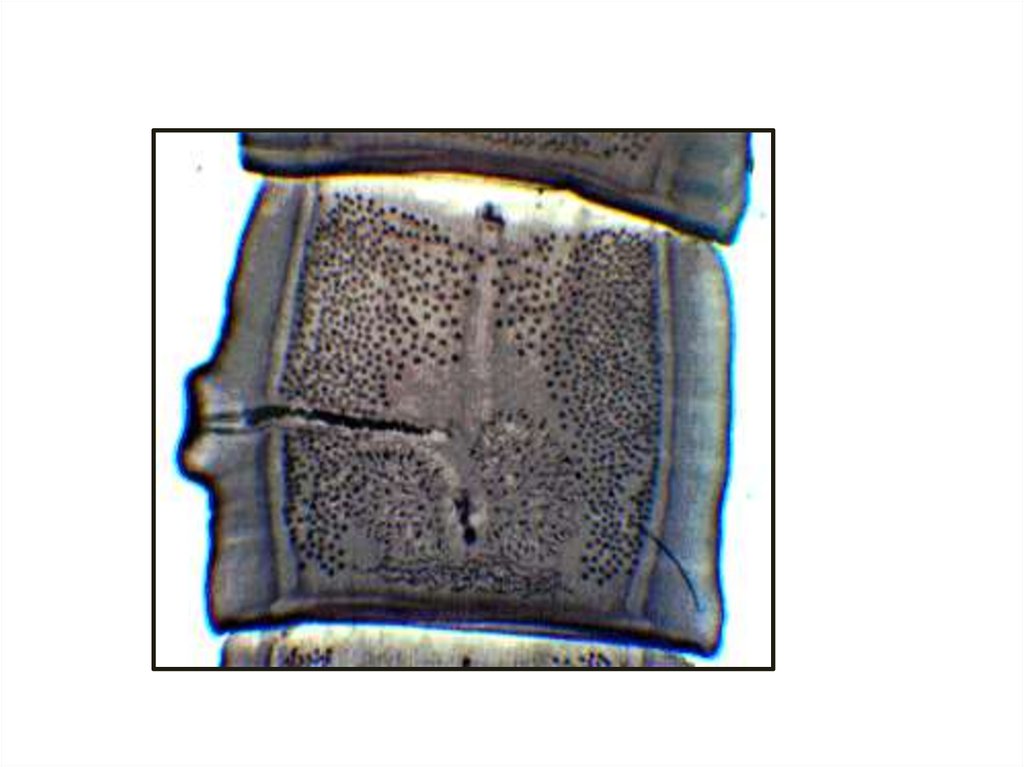

Микро- и макропрепараты